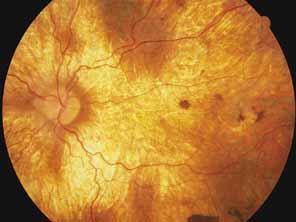

Serpiginous choroidopathy, also called serpiginous choroiditis, is a recurrent, progressive, destructive chronic degeneration of the choroid and retinal pigment epithelium that begins around the optic nerve and extends through the posterior pole.44 Unfortunately, some cases of this disorder have been reported under the name geographic helicoid peripapillary choroidopathy, and this has led to confusion with the clearly dominantly inherited genetic disorder first described in Iceland by Sveinsson26 in 1939 as choroiditis areata and subsequently renamed helicoidal peripapillary chorioretinal degeneration.27,28 The etiology of serpiginous choroidopathy is unknown, but the disease is not thought to be genetic. The disease starts as a gray, cream, or greenish discoloration and edema of the retinal pigment epithelium, followed by extension of the lesion, usually away from the disc, in a stepwise fashion (Figs. 8A and 8B). Vitritis is present in one-third of cases. Periods of quiescence or activity can be separated by months to years. Subretinal fibrous scarring, atrophy of the choroid, and hyperpigmentation in adjacent tissues can be prominent features (Figs. 8C and 8D). The prognosis for retention of central vision is poor because the disease process will often involve the macula. Systemic immunosuppression may be effective in prolonging remission and improving the visual outcome.45

Fig. 8 Right fundus (A) and late-phase fluorescein angiogram (B) of a 35-year-old woman with serpiginous choroidopathy. The visual acuity was 20/200. Left fundus (C) and fluorescein angiogram (D) of a 47-year-old man with advanced serpiginous choroidopathy, demonstrating several stages of lesions and subretinal gliosis. Visual acuity was 14/400. (A and B courtesy of Michael L. Klein, M.D., Portland, OR)